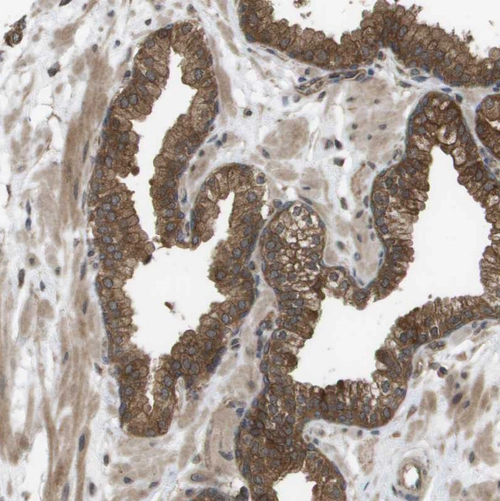

Immunohistochemical staining of human endometrium shows strong cytoplasmic positivity in glandular cells.